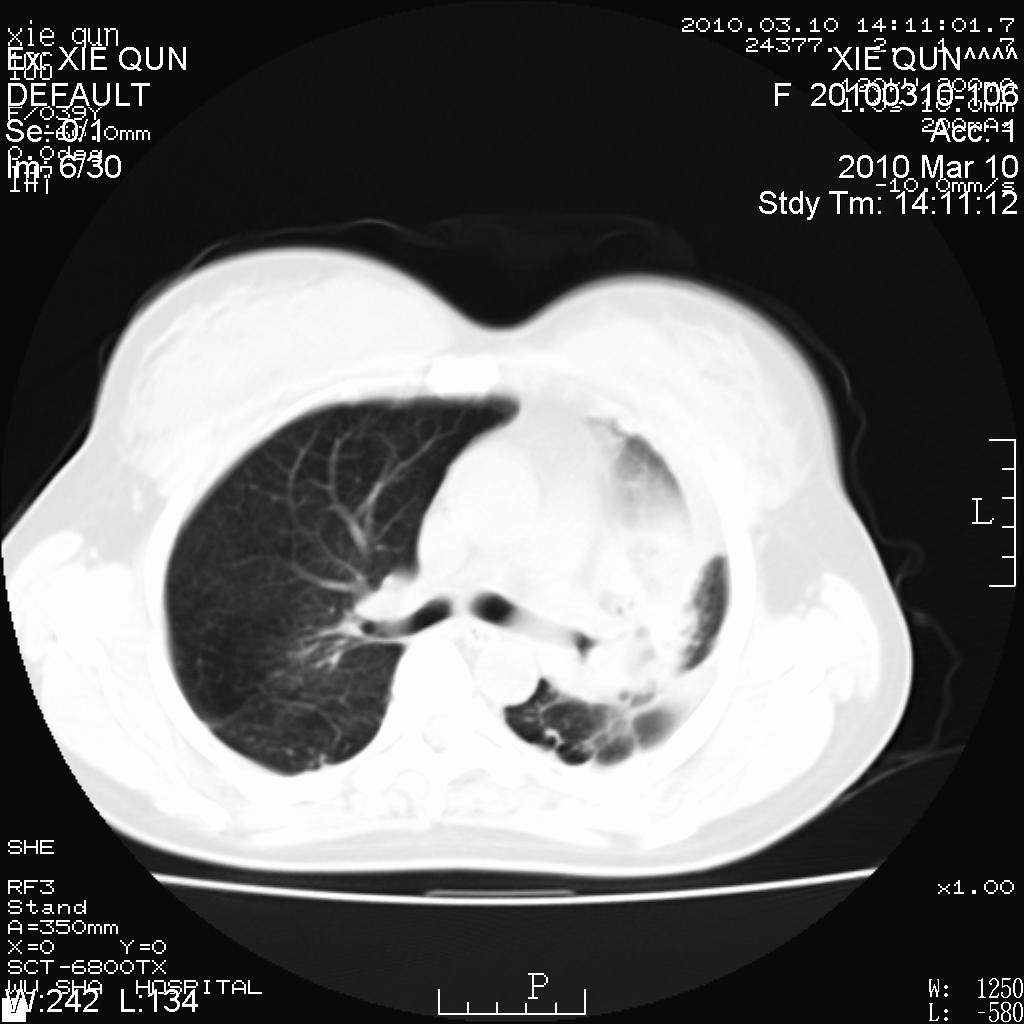

以下是引用心路寻觅在2010-3-24 17:28:00的发言:[br]两肺继发性tb左上肺空洞形成,建议痰检明确诊断。

以下是引用随光逐影在2010-3-24 19:19:00的发言:[br]两肺继发性结核并左上肺上叶空洞形成。